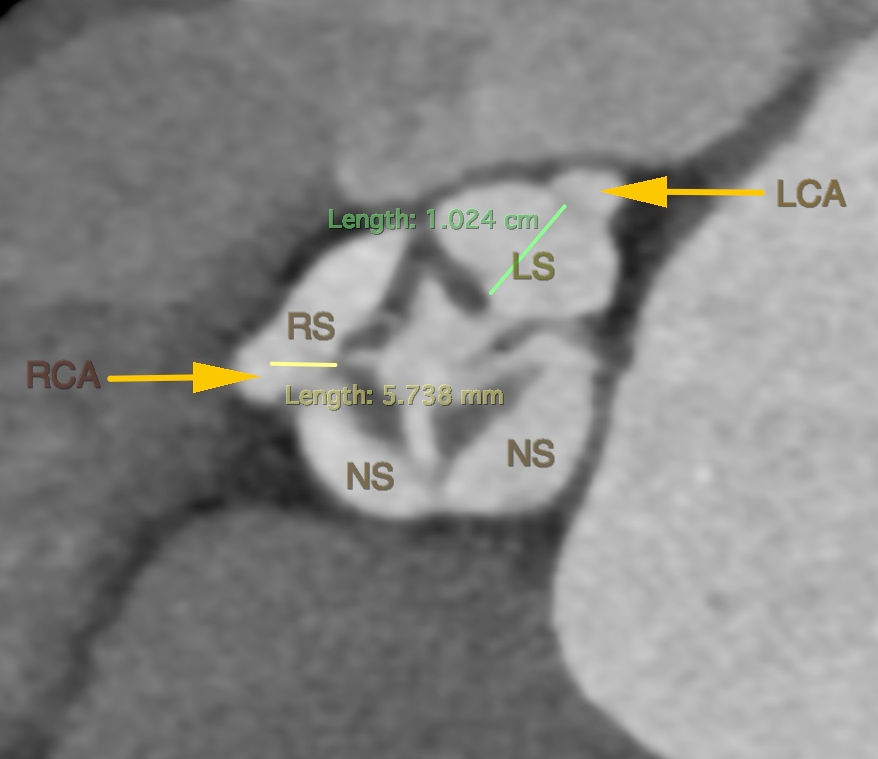

CT评估

• CT显示分布的四叶瓣,瓣窦较小,冠脉开口较低,瓣叶冗长增厚,左右冠瓣叶长度均超过STJ高度。

图片

主动脉根部情况

• 术前CT预估21mm人工瓣膜植入后位置及STJ层面残余空间。患者右-无、双无冠状窦少量粘连,预计瓣膜植入后向左右冠窦方向偏移。